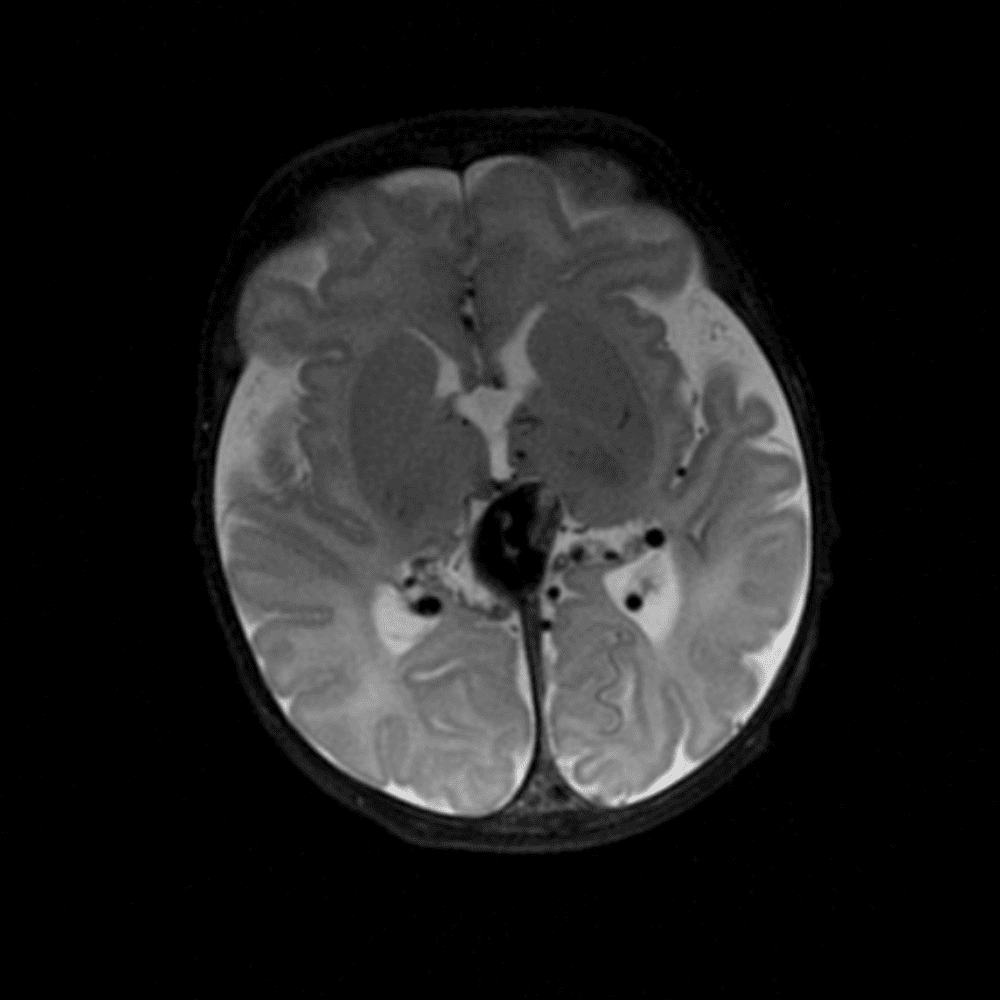

๋‹น์ง ์‹œ ํ”ํžˆ ๋ณผ ์ˆ˜ ์žˆ๋Š” ์‚ฌ๋ก€์˜ ์ „ํ˜•์ ์ธ ์˜ˆ๋ฅผ ํฌํ•จํ•ฉ๋‹ˆ๋‹ค.

39 ์‚ฌ๋ก€

์—ฐ์Šต

๋ฏธ๋ฌ˜ํ•˜๊ฑฐ๋‚˜ ์–ด๋ ค์šด ์‚ฌ๋ก€์™€ ์ผ๋ถ€ ์ •์ƒ ์‚ฌ๋ก€๋ฅผ ํฌํ•จํ•˜์—ฌ ๋‹น์ง์„ ์‹œ๋ฎฌ๋ ˆ์ด์…˜ํ•ฉ๋‹ˆ๋‹ค.

50 ์‚ฌ๋ก€